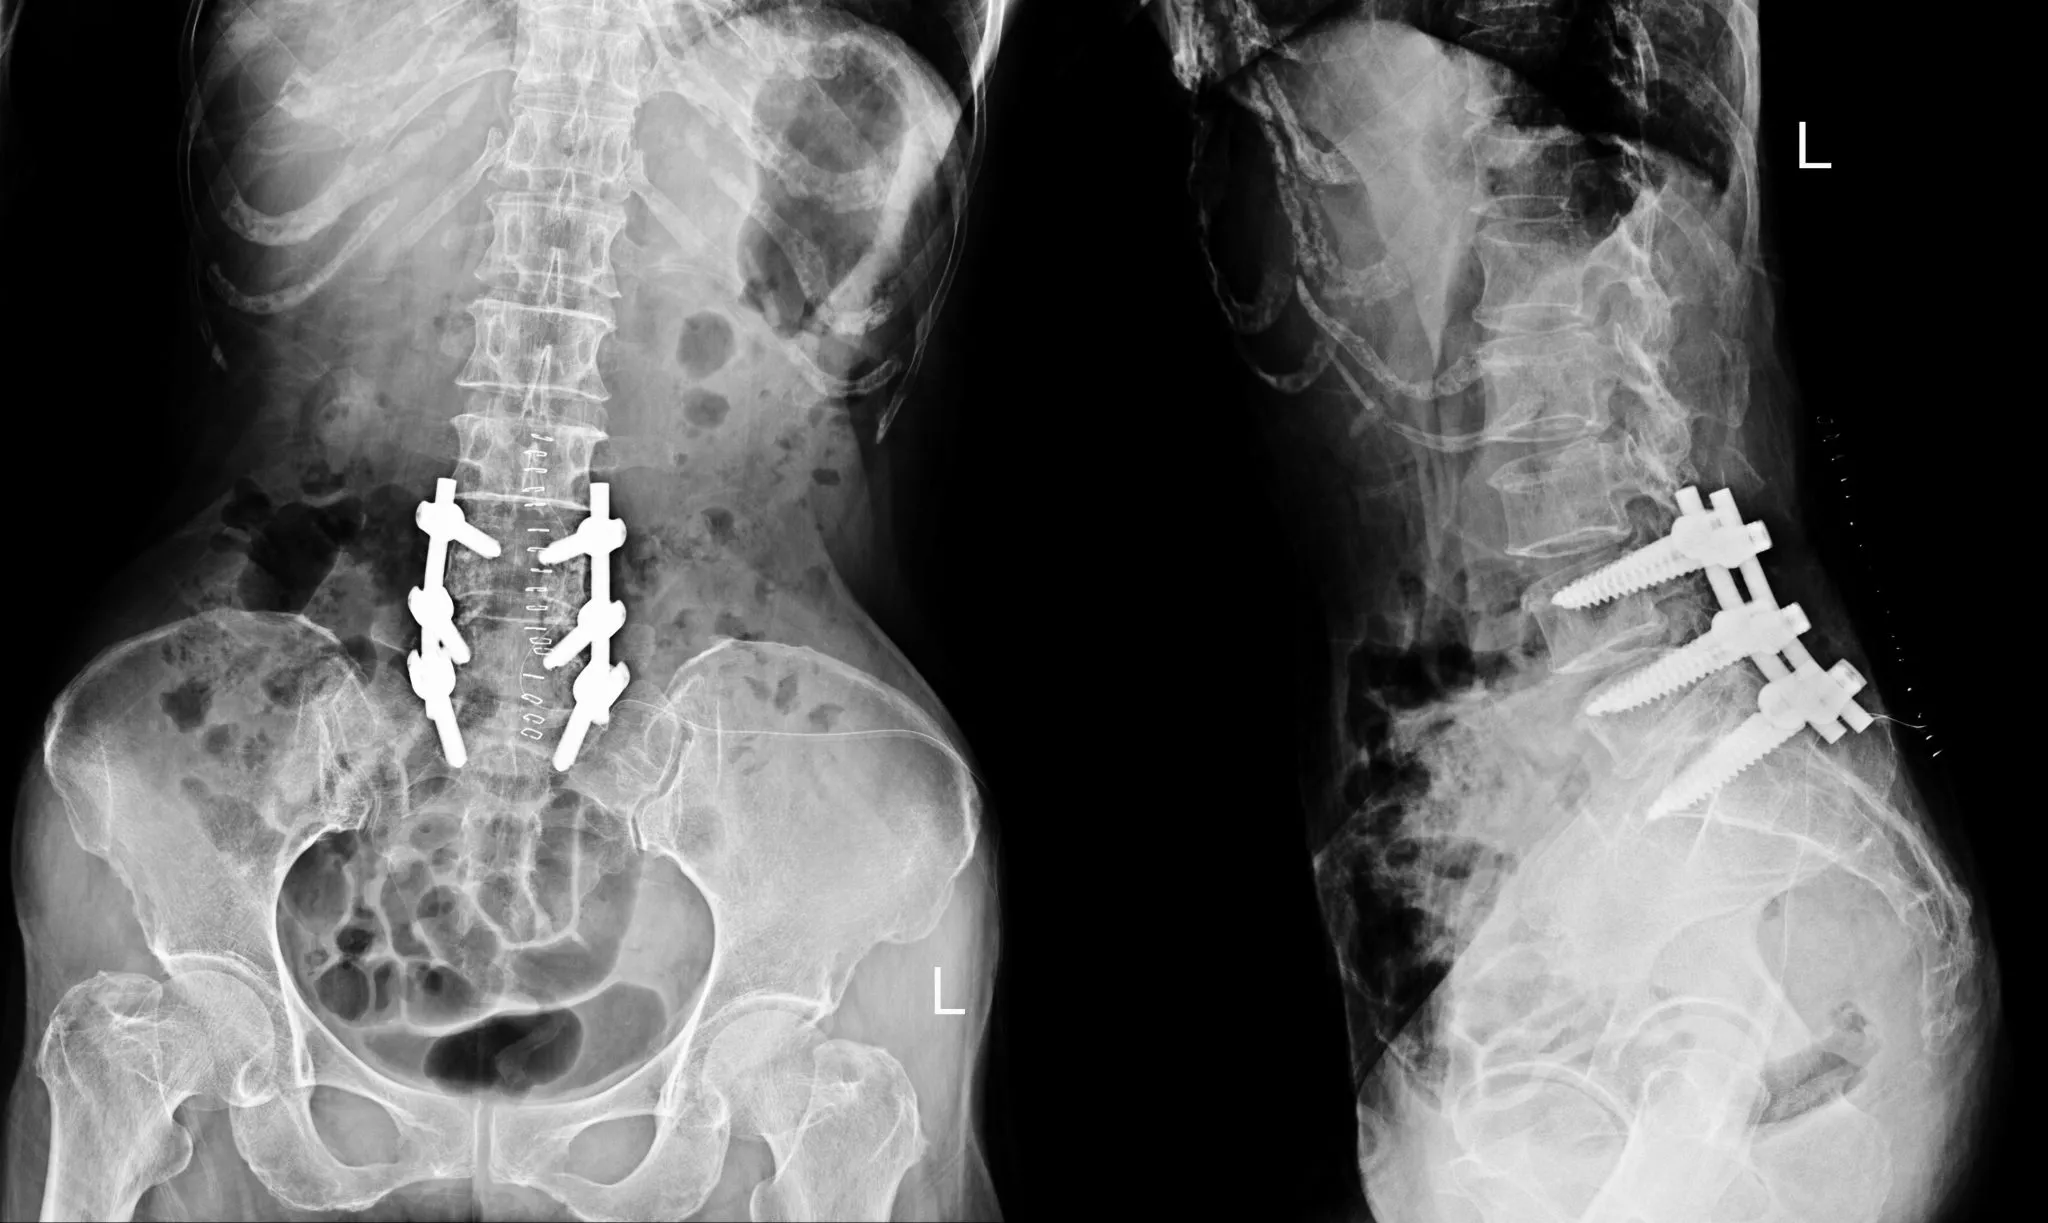

Spinal fusion surgery is a traditional approach to treating conditions such as herniated discs, sciatica, degenerative disc disease, and spinal stenosis. During this procedure, two or more vertebrae are permanently joined using metal hardware (screws, rods, and cages) along with bone grafts. The goal is to eliminate motion at a painful segment of the spine.

During a spinal fusion procedure, surgeons access the spine through various approaches. They remove the damaged disc material, prepare the vertebral surfaces, place bone graft material between the vertebrae, and secure everything with metal hardware to hold the vertebrae in position while the bone graft heals and forms a solid bony bridge.

The fusion process takes approximately 3–6 months, during which the vertebrae gradually grow together. Once complete, these vertebrae function as a single, solid bone segment, permanently eliminating motion at that level.

Hardware Complications

Screws, rods, and cages can fail, shift, loosen, or even cause allergic reactions in some patients. Hardware complications include:

Screw loosening or pullout: The screws anchoring the construct can loosen from the bone, causing pain and instability

Rod fracture: The metal rods connecting the screws can break under stress, particularly in long fusions

Cage subsidence: The interbody cages placed between vertebrae can sink into the vertebral body, losing height and potentially compressing nerves

Hardware prominence: Screws or rods can become prominent under the skin, causing discomfort and sometimes requiring removal

Allergic reactions: Though rare, some patients develop metal sensitivity or allergic reactions to titanium or other hardware materials

A 2023 study examining the influence of screw positioning found that proper hardware placement is critical for preventing cage subsidence and maintaining fusion integrity.